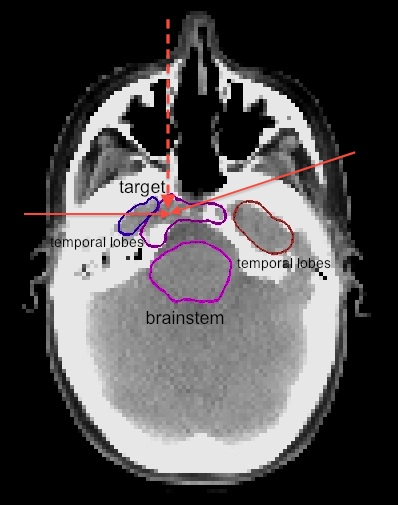

3.1 Base of skull

A representative CT slice of the patient is shown in Figure 1. Three proton beams are used in the plan for the base of skull case. Two beams are in the transverse plane at gantry angles of 75 and 270 degrees. The third one is an obliquely incident superior-anterior beam, which is at a couch angle of 90 degrees and gantry angle of 300 degrees. The total number of beamlets is 7,778. The dose grid is 12512599 voxels. The voxel size is 2.5 mm 2.5 mm 2.5 mm. We assume 3 mm setup uncertainty and 3.5% range uncertainty. For robust optimization we use 9 error scenarios as defined in section 2.2.2. The raw dose-fluence matrices of the 9 scenarios total to 11 Gb in size.